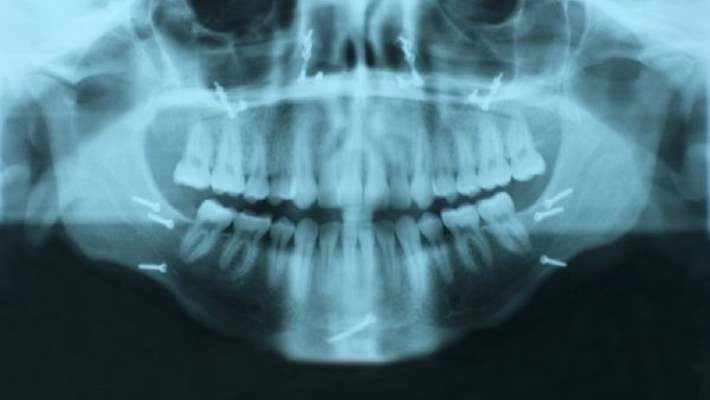

Çene Kırığının Tıbbi Tedavisi

Çene ağrısı olan birçok kişide çene kırığı yoktur; bu durum ağrı ilaçları, kolay çiğnenebilen gıdalar, beslenme talimatları ve doktor takibiyle tedavi edilir.

- Kırığı olanlar daha ileri değerlendirmeye ihtiyaç duyarlar. Çene kemiği kırıklarının çoğu, dişeti sorunları ve doku zedelenmeleriyle ilişkilidir ve enfeksiyon riskine açık kırıklar olarak değerlendirilmelidir.

- Birçok çene kırığı sabittir ve gereken tedavi sadece alt ve üst dişlere birlikte tel takılmasıyla olur. Bunun yapılabilmesiyse yaygın kullanılan ağız ve çene cerrahisi uygulamasını gerektirir.

- Daha stabil olmayan kırıklarsa cerrahi müdahale gerektirir. Kırık bölgelerde levha kullanan cerrahi yöntemler, cerrahiden kısa bir süre sonra çenenizi normal bir şekilde hareket ettirme ve yemek yeme imkanı sağlar.